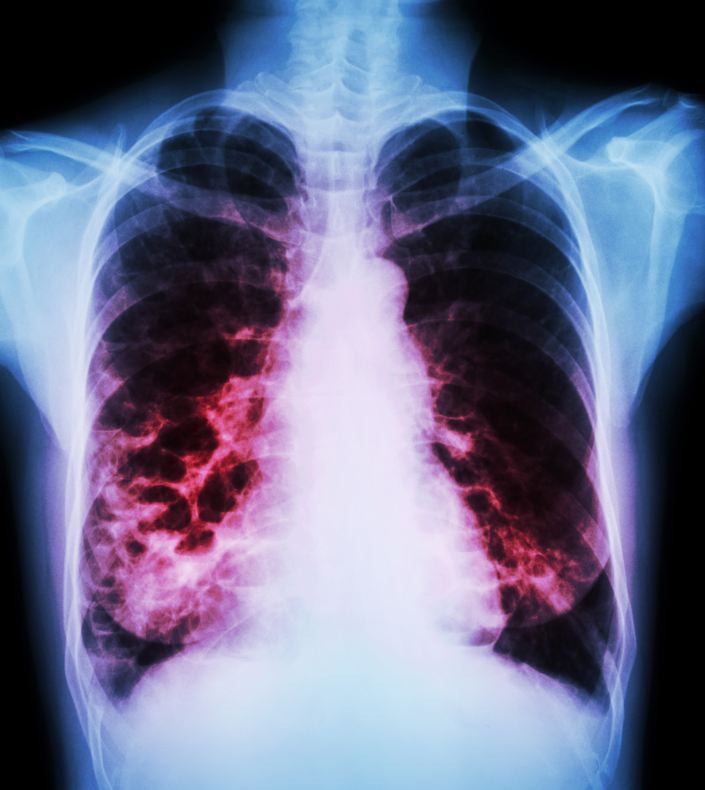

Infections with pneumonia send a substantial number of older adults to the hospital, much more than younger adults. Researchers are calling for new rapid diagnostic tests.

Three studies culled from the very recent literature offer insights into prevention and treatment of pneumonia in adults. Highlights in this slide show.

Health care–associated pneumonia (HCAP) is a relatively new term used to describe pneumonia that develops in patients who have recently been exposed to nosocomial and drug-resistant pathogens as a result of hospitalization or residence in a nursing home, for example. A recent study found that about 25% of patients hospitalized with pneumonia had HCAP, and that the mortality rate was higher in those with HCAP than in those with community-acquired pneumonia (CAP).